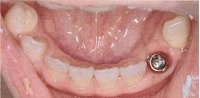

当院のインプラント症例(1本失った場合)

インプラント症例(1本失った場合)①術前

インプラント症例(1本失った場合)①術後